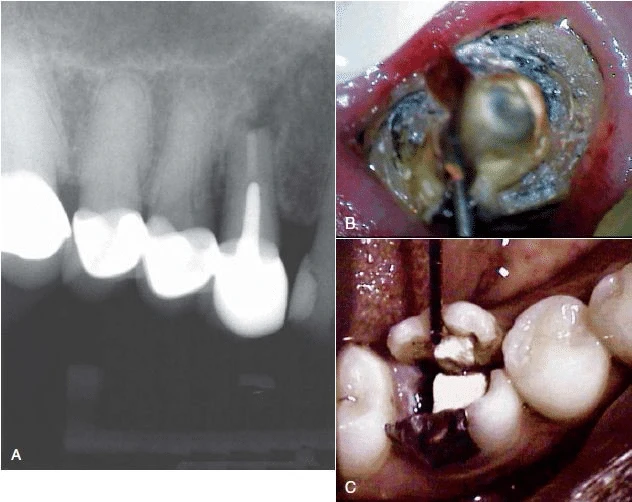

Do vùng nứt phía chóp răng, miếng trám ngược ống tuỷ sẽ sút ra. Điều trị nội nha tốt nhưng tổn thương không được chữa lành cũng có thể gợi ý nứt dọc chân răng, đặc biệt nếu răng vẫn không lành khi điều trị lại hoặc phẫu thuật cắt chóp.

Hình 3. Nhiễm trùng tuỷ răng tái phát sau điều trị nội nha có thể là do nứt dọc chân răng